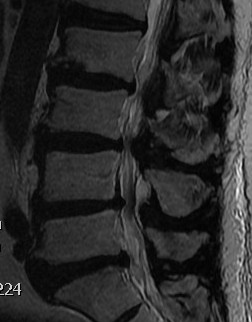

MRI

T2 Sagittal "MRI Myelogram"

Intervertebral foramina

- no fat about nerve root

- reduced height